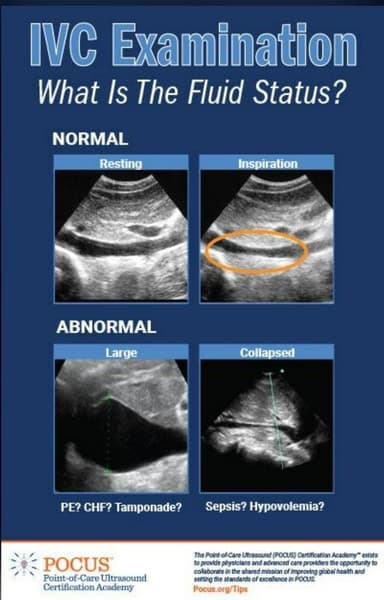

This video presents a sonogram of a patient's abdomen, with a particular emphasis on the Inferior Vena Cava (IVC)鈥攖he major vein responsible for transporting deoxygenated blood back to the heart. In a healthy person, the IVC is a pliable vessel that 'collapses' or slightly narrows during inhalation due to variations in thoracic pressure. The vessel appears wide and 'rigid.' It does not significantly alter its shape with the patient's breathing. This absence of collapse is commonly referred to as a 'plethoric IVC.' Typically, this condition suggests elevated central venous pressure. When a clinician observes a dilated, non-collapsing IVC in a patient experiencing acute pain, they are often investigating for Cardiac Tamponade, Pulmonary Embolism, or Congestive Heart Failure.